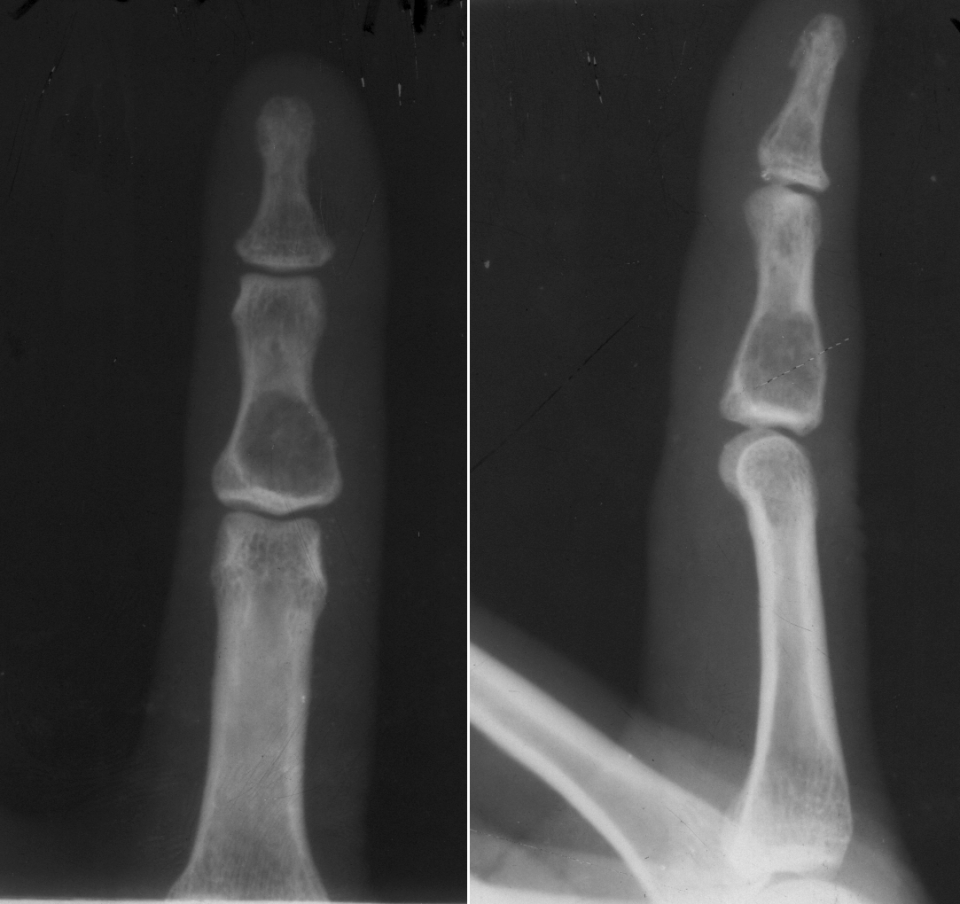

地图样破坏是指肿瘤组织在一个局部呈团块状生长造成界限清楚的骨质破坏(图 1、图 2、图 3、图 4)。病灶可位于骨的中心或一侧部位,呈圆形、卵圆形密度减低区,与正常骨质分界清晰,边缘可有或无硬化带围绕,骨的形态无变化,病灶内可完全透亮或可见粗细不均、大小不等的残留骨嵴,内缘可光滑或呈分叶状压迹。地图样破坏见于大多数良性肿瘤和肿瘤样病变如单纯性骨囊肿、骨纤维结构不良、血管瘤等、也可见于部分恶性骨肿瘤如骨转移瘤、骨髓瘤等。

图片

图 1.地图样破坏:单纯性骨囊肿